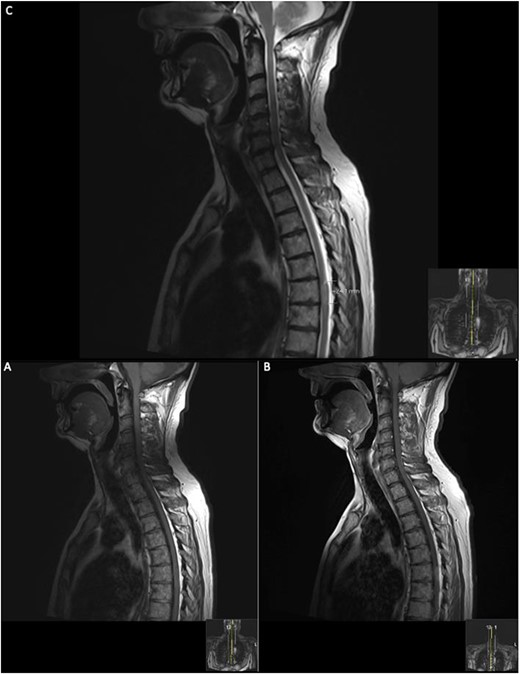

Repeat contrasted MRI whole spine; demonstrates findings consistent with spinal cord meningioma at the level of T6; this can be clearly visualized by comparing the T1 sagittal pre-contrast (A) with a T1 sagittal post-contrast (B), where a clearly demarcated lesion can be seen at the level of T6; this is supported further by the sagittal T2 image (C) shown where an ~24 mm lesion can be seen at T6.